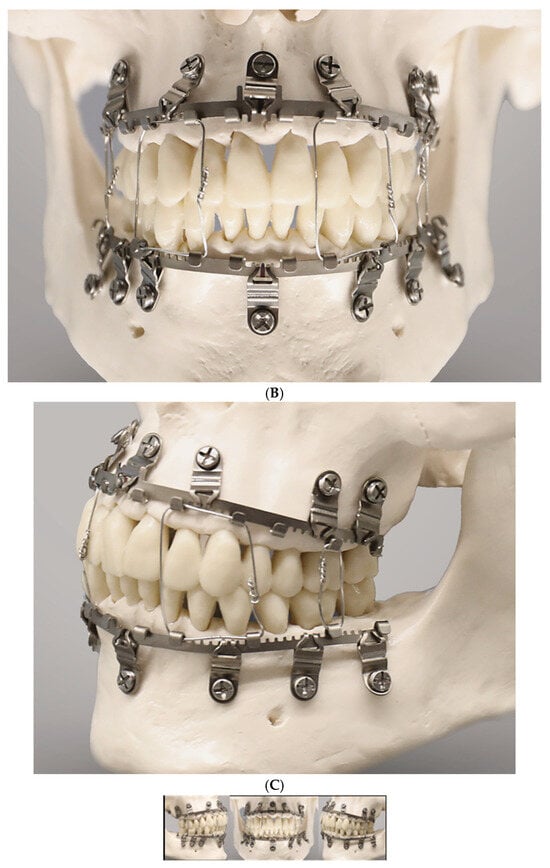

Figure 2.

(A) Clinical case example—Stryker SMARTLock Hybrid MMF System (regular size) in situ in a right condylar base fracture of the mandible. The arch bars are not shortened; several support legs (‘lugs’) have been bent along the length of their vertical axis to superimpose the screw-receiving holes over the interradicular spaces; all holes except from the right lower 2nd molar are filled with bone screws; the screws are lined up below the mucogingival junction in the upper jaw; in the mandible, the vestibules become shallow along the posterior bucco-alveolar sulcus, so these screws are placed in the mobile mucosa; in the anterior vestibulum, the screws are located low to reach down into the opening interradicular spaces; with such deep placement, the tooth equators cannot be attained. Preinjury occlusion with a lateral crossbite on the left is reestablished and maintained with anterior criss-cross elastic loop intermaxillary fixation. Note the kinking at the base of several bent supporting legs (‘lugs’). (B) Immediate postoperative panoramic X-ray after placement of SMARTLock arch bars. Miniplate fixation of right condylar base fracture (ORIF). Interradicular position of all arch bar retaining screws. In the upper right quadrant, 2 screws projecting over maxillary sinus. Eyelet of supporting leg (‘lug’) over right lower 2nd molar empty. Source/origin: Photograph collection—C.P. Cornelius.

The OmniMax MMF System (Zimmer-Biomet, Jacksonville, FL, USA) is a bone-anchored MMF system and is composed of preformed arch bars (plates) and locking screws based on the same basic principle as other hybrid systems (Figure 3). The market release was in 2016.

Figure 3.

Arrangement of OmniMax arch bars (plates) for application on the mandible and maxillae together with self-drilling locking screws. The plates are preformed by in-plane bending into slight curves. The screws are placed for fixation in the anterolateral transition and the posterior portion of the jaws. At best, no more than two slots in sequence are left empty. Source/origin: Photograph collection—C.P. Cornelius.

The core diameter of the annular groove is larger than the diameter of the second thread set and is sized for a tight fit within the beveled rims of the slot aperture of the plate (arch bar) (Figure 3 and Figure 4). These properties of the OmniMax screw are the basis for the plate’s standoff feature, which creates a gap between the plate and the gingivo-mucosal surface.

Figure 4.

(A) Clinical case example—intraoperative view of Zimmer Biomet OmniMax MMF devices divided into 4 segments for treatment of a triple mandibular fracture—bilateral condylar base and symphyseal midline. A dental splint (Titanium Trauma Splint, Medartis, Basel, Switzerland) resin bonded (acid etching technique) to the outer surfaces of the teeth of the anterior maxillary arch supports the repositioned medial upper incisors. The two maxillary segments represent the shortest possible plate variant consisting of a single mounting tab containing two slot apertures, with 2.0 four-hole miniplate visible in open anterior vestibulum approach. Of note: the standoff mechanism has been implemented for all screws—annular screw grooves fully seated in the slots. (B) Previous case cont’d. Postoperative panoramic X-ray after placement of OmniMax arch bars, ORIF—via transoral vestibular and preauricular transparotid approaches. Miniplate fixation of the condylar base fractures. Four-hole superior border (tension band) miniplate fixation in combination with a six-hole 2.4 inferior border plate. The arch bar retaining screws appear inserted correctly in the interradicular spaces. Source/origin: Photograph collection—C.P. Cornelius.

During continuous insertion of an OmniMax self-drilling screw, the second thread portion will engage the rim of the slot aperture. Owing to the different lead of the threads, with further advancement into the bone, the plate will be raised towards the head of the screw until the rim of the slot will be finally seated into the annular retention groove of the screw and held there by tight friction. For the plate, once seated within the screw’s locking groove, the standoff height can be tuned by turning the screw out of or into the bone. The gap can be further established and adjusted without a spacer tool.